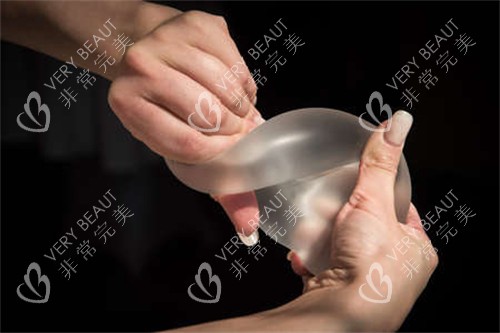

魏家宾院长专攻曼托、傲诺拉等高端假体,可根据每位顾客的胸廓、皮肤张力等个性化特征量身定制手术方案,术后结果自然逼真,触感柔软如原生胸。

在个性化定制方面,魏院长会根据每位顾客的胸廓宽度、皮肤弹性、组织厚度等参数,结合人体美学比例,从曼托、傲诺拉、法芮娅等高端假体品牌中选择比较适合的型号和植入层次,即使是体型瘦小的顾客也能实现从A杯到C杯的自然过渡。

在假体选择上,提供从经济型到头部品牌的完整产品线,包括美国曼托、傲诺拉璀璨/耀绚系列、法国ES以及头部法芮娅假体等,满足不同预算和需求的顾客。

医院拥有独立的假体展示中心,顾客可以直观了解各种假体的特点和触感。